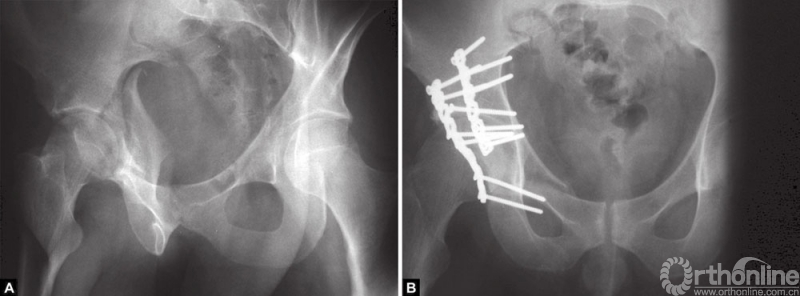

A和B(A)前方入路固定横行骨折;(B)骨盆内钢丝环扎

32岁男性患者,高处坠落伤后左侧髋臼出现横行骨折。采用髂腹股沟入路处理骨折。采用骨盆内钢丝环扎辅助复位和固定骨折。